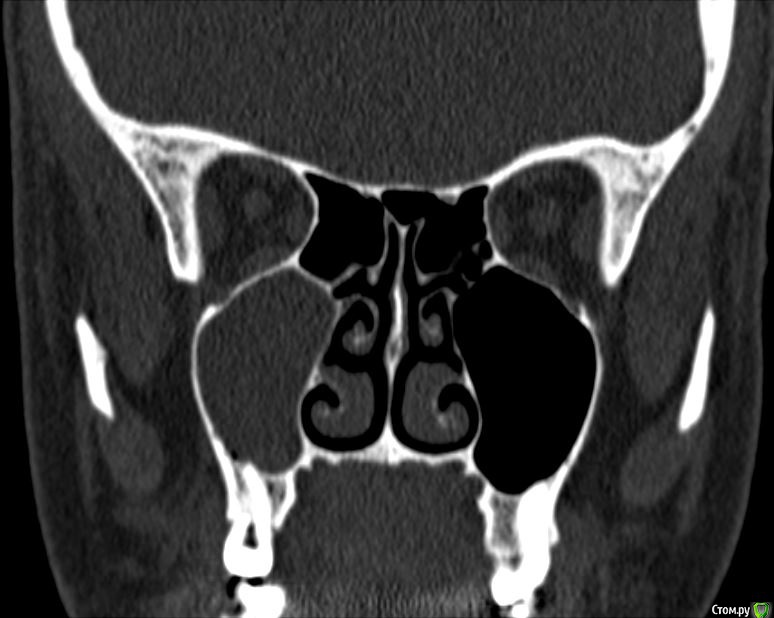

Лисица Опубликовано 26 июля, 2015 Автор Поделиться Опубликовано 26 июля, 2015 (изменено) Вы же не думаете, что Вам назначат а/б терапию по интернету? Я просто не знаю, исходя из каких показателей она назначается. Поэтому осведомилась на всякий случай. Итак, сходила я сегодня на КТ. И по ходу мне сделали что-то не то... Когда я обратилась в клинику, я уточнила, что мне нужно КТ для эндодонтии, чтобы видно было каналы, с достаточным разрешением, чтобы было видно зубы и их корни, входящие в верхнечелюстной синус. Администратор клиники уточнила у врача и сказала, что мне нужно заказывать не КТ верхней челюсти, а КТ пазух. У рентгенолога я также повторила все описанное, рассказала, что при лечении каналов вчера была продырявлена пазуха, уточнила, будут ли видны как следует зубы и их каналы, меня заверили, что "все будет". Причем у врача, судя по описанию на сайте клиники, была ординатура по хирургии в медико-стоматологическом университете, так что он, уж наверное, понимал, что мне нужно. В итоге я получила пленку со снимками формата чуть ли не А3 и диск. На пленке все зубы были просто белыми и коронки видны не целиком. Заключение: в правой верхнечелюстной пазухе уровень жидкости, острый правосторонний гайморит.Думала, может в программе можно будет увеличить разрешение. Но похоже, что нет... или я просто ламер? Зубы просто размытые и белые... Прилагаю сделанные мной скриншоты, как мне кажется, наиболее показательные... Если нужно другие "виды", то скажите какие, или такие снимки вообще ни о чем? Программа просмотра называется Philips DICOM Viewer R3.0-SP03. Аппарат был не местный "на голову", а здоровый, куда заезжаешь в лежачем положении. Изменено 26 июля, 2015 пользователем Лисица Ссылка на комментарий

St. Опубликовано 27 июля, 2015 Поделиться Опубликовано 27 июля, 2015 Гайморит справа есть, и жидкость тоже. Корни этого зуба действительно заканчиваются в гайморовой.Ничего такого страшного, чтоб однозначно удалять зуб я не вижу. С гайморитом - к лорам на лечение.В зубе я бы ещё раз поменяла лекарство на пару недель, пока гайморит не притихнет, потом постоянно пломбировать. 1 Ссылка на комментарий

Лисица Опубликовано 27 июля, 2015 Автор Поделиться Опубликовано 27 июля, 2015 St., большое спасибо за ответ! Моя врач планировала закрыть его в среду (зная о том, что пазуха проткнута). Если запломбировать, пока воспаление есть, какие могут быть проблемы? И еще она сказала, что нащупала 4-й тонкий канал, но не было времени его прочистить, так что она оставила как есть до среды. Сказала, что почистит и сразу же закроет. Судя по КТ, корня 3, значит в одном из них 2 канала? В 3D похоже, что корни с медиальной стороны сросшиеся какие-то... и на небном тоже борозда. Ссылка на комментарий